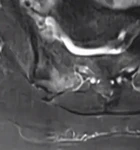

Resim 2. Sakroiliak MRG'de sakrum sağında intansite artışı (ekleme komşu olmayan bölgede).

Resim 4. Sakroiliak MRG aksiyal kesitte sakrum sağında belirgin hiperintens alan.